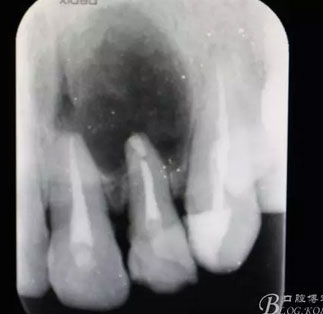

圖1.術(shù)前患者的x光根尖片檢查影像:22根尖完全位于囊腔內(nèi),牙槽骨吸收至嵴頂約5mm。22松動Ⅰ度。

圖20.術(shù)后的根尖片:22根尖MTA倒充填、21根尖切除術(shù)。